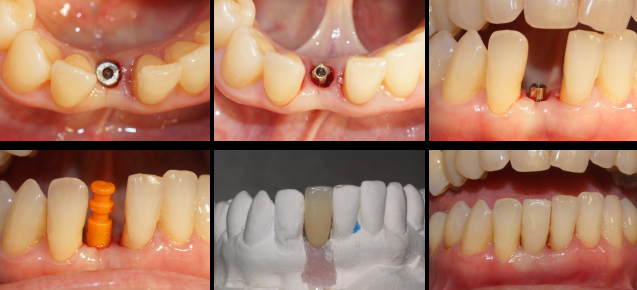

Após 35 dias da instalação do implante foi realizada a abertura do implante através de um bisturi circular e o pilar Ideale reto de 3.3 X 4.0 X 2.5 mm foi torqueado no implante a 20 Ncm. Foi realizada também uma moldagem deste pilar com o seu transferente correspondente e a prótese adesiva voltou a ser instalada. Depois de uma semana, o provisório parafusado confeccionado no laboratório foi instalado e mantido em posição durante 15 dias para formar um novo perfil de emergência, aproximando as características dos tecidos circundantes às características de um incisivo central inferior. Neste momento, foi realizada uma nova moldagem da região e uma coroa metalocerâmica foi confeccionada e instalada após uma semana. Foi também realizada a radiografia.

O resultado clínico alcançado com sucesso foi fruto das escolhas corretas durante o planejamento cirúrgico/protético e somente apresentou essas características clinicas de naturalidade por ser uma conexão Cone Morse e por ter um pilar protético mais estreito do que o diâmetro do implante.